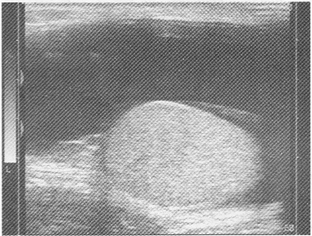

4.某患者陰囊超聲檢查圖像如下,最可能的診斷是

A.睪丸鞘膜積液

B.精索鞘膜積液

C.陰囊水腫

D.附睪較大囊腫

E.交通性鞘膜積液

正確答案:A解題思路:陰囊內見無回聲暗區,睪丸附著于鞘膜囊的一側,液體三面包繞睪丸周圍。